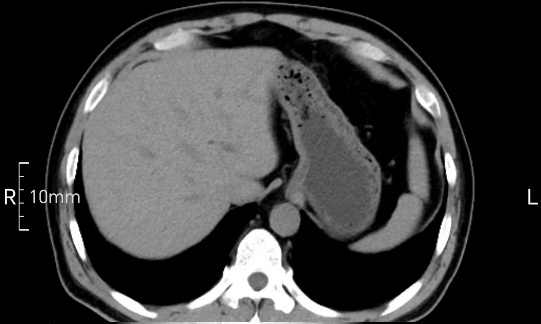

沒禁食,胃內全是食物,導致胃壁顯示不清。

禁食但檢查前沒有喝飽,胃未能漲開,胃壁觀察效果不佳。

完美禁食且喝飽飽,胃壁完美展現。